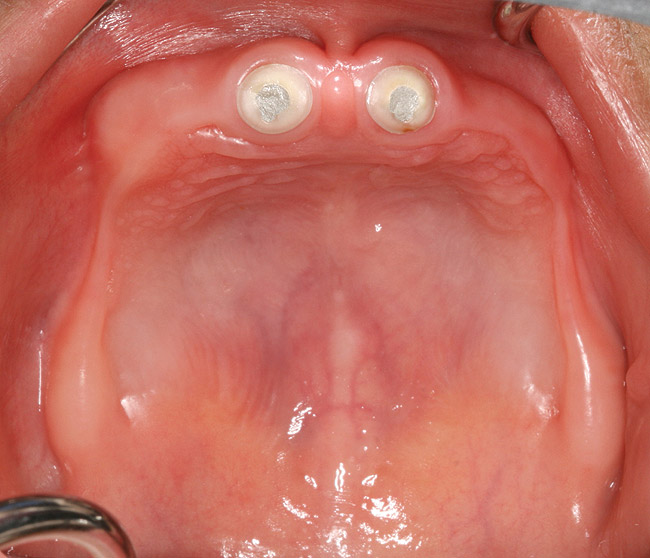

Figure 6  Maxillary alveolar ridge after endodontic therapy and crown amputation of the maxillary central incisors.

Figure 6